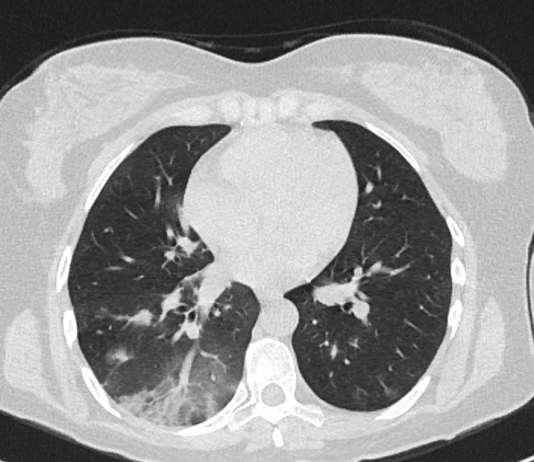

Maschio, 51 anni. Anamnesi patologica remota muta. Il paziente è residente a Fabrizia,...

Maschio, 51 anni. Anamnesi patologica...